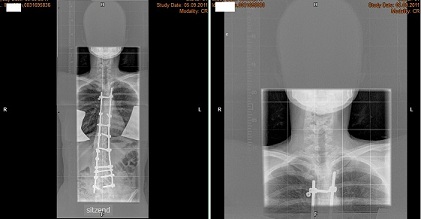

Das sind keine Harrington-Stäbe, vgl. den folgenden Anhang.

Harrington, 2 Stäbe.jpg

Harrington, 2 Stäbe.jpg (26.55 KiB) 5417 mal betrachtet

Nee, da ist eigentlich nicht viel Ähnlichkeit. Ein Harrington-Stab wird mit zwei Haken an den Fortsätzen der Wirbel befestigt, aber die Stangen auf den Röntgenbildern von Dir sind mit Pedikelschrauben fixiert, die direkt in den Wirbelkörpern sind. Das ist ein ganz anderes Prinzip. Der genaue Implantattyp müßte irgendwo in den OP-Unterlagen oder im Arztbericht zu finden sein.